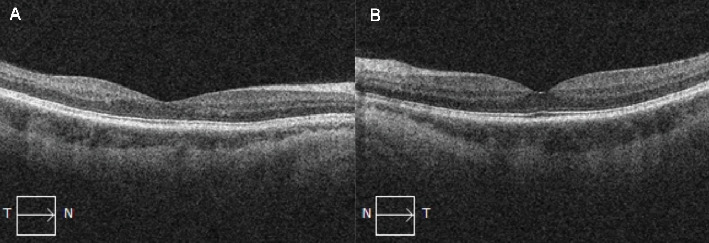

Purpose: The purpose of the study is to present a case of central retinal vein occlusion (CRVO) associated with the use of progestin-only contraceptive implant. Methods: The study is a case report. Results: This is a case of a 34-year-old Caucasian female nonsmoker who presented with sudden-onset painless blurring of vision of the left eye. There were no associated ocular and systemic signs or symptoms. She has no comorbidities. The patient disclosed that she was on the etonogestrel implant, a progestin-only contraceptive, at the time of consult. She was previously diagnosed with a CRVO of the right eye while on the combined hormonal contraceptive in 2017. She had a best corrected visual acuity (BCVA) of 6/6 in both eyes. Anterior segment examinations of both eyes were unremarkable. Fundus examination of the right eye revealed normal findings; however, the fundus exam of the left eye showed a clear media with a healthy looking disc but with sparse dot blot hemorrhages in all retinal quadrants and dilated and tortuous retinal vessels, along with a healthy-looking macula. Macular optical coherence tomography (OCT) did not show any signs of macular edema. Carotid ultrasound, autoimmune, and coagulation panels were all normal. Subsequent visits showed complete resolution of the retinal hemorrhages, and the retinal vasculature returned to normal anatomical configuration. A diagnosis of left CRVO secondary to etonogestrel implant was made. Conclusion: This study recognized that the use of progestin-only contraceptives still has an increased risk of thrombosis. It is essential to consider the mode of administration and duration of use of these contraceptives.